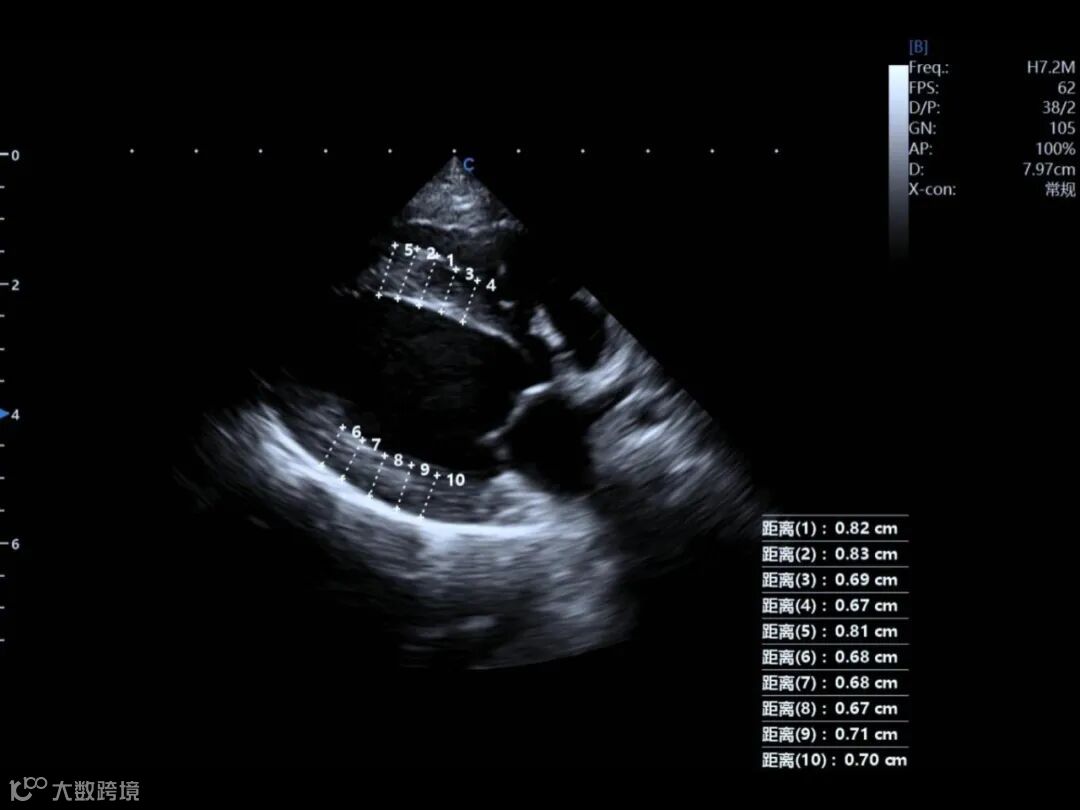

1. Severe Asymmetric Hypertrophy

Both the interventricular septum (IVSd) and left ventricular posterior wall (LVPWd) were significantly thickened, each exceeding 0.6 cm.

This pattern is characteristic of HOCM, where diastolic filling becomes progressively impaired.